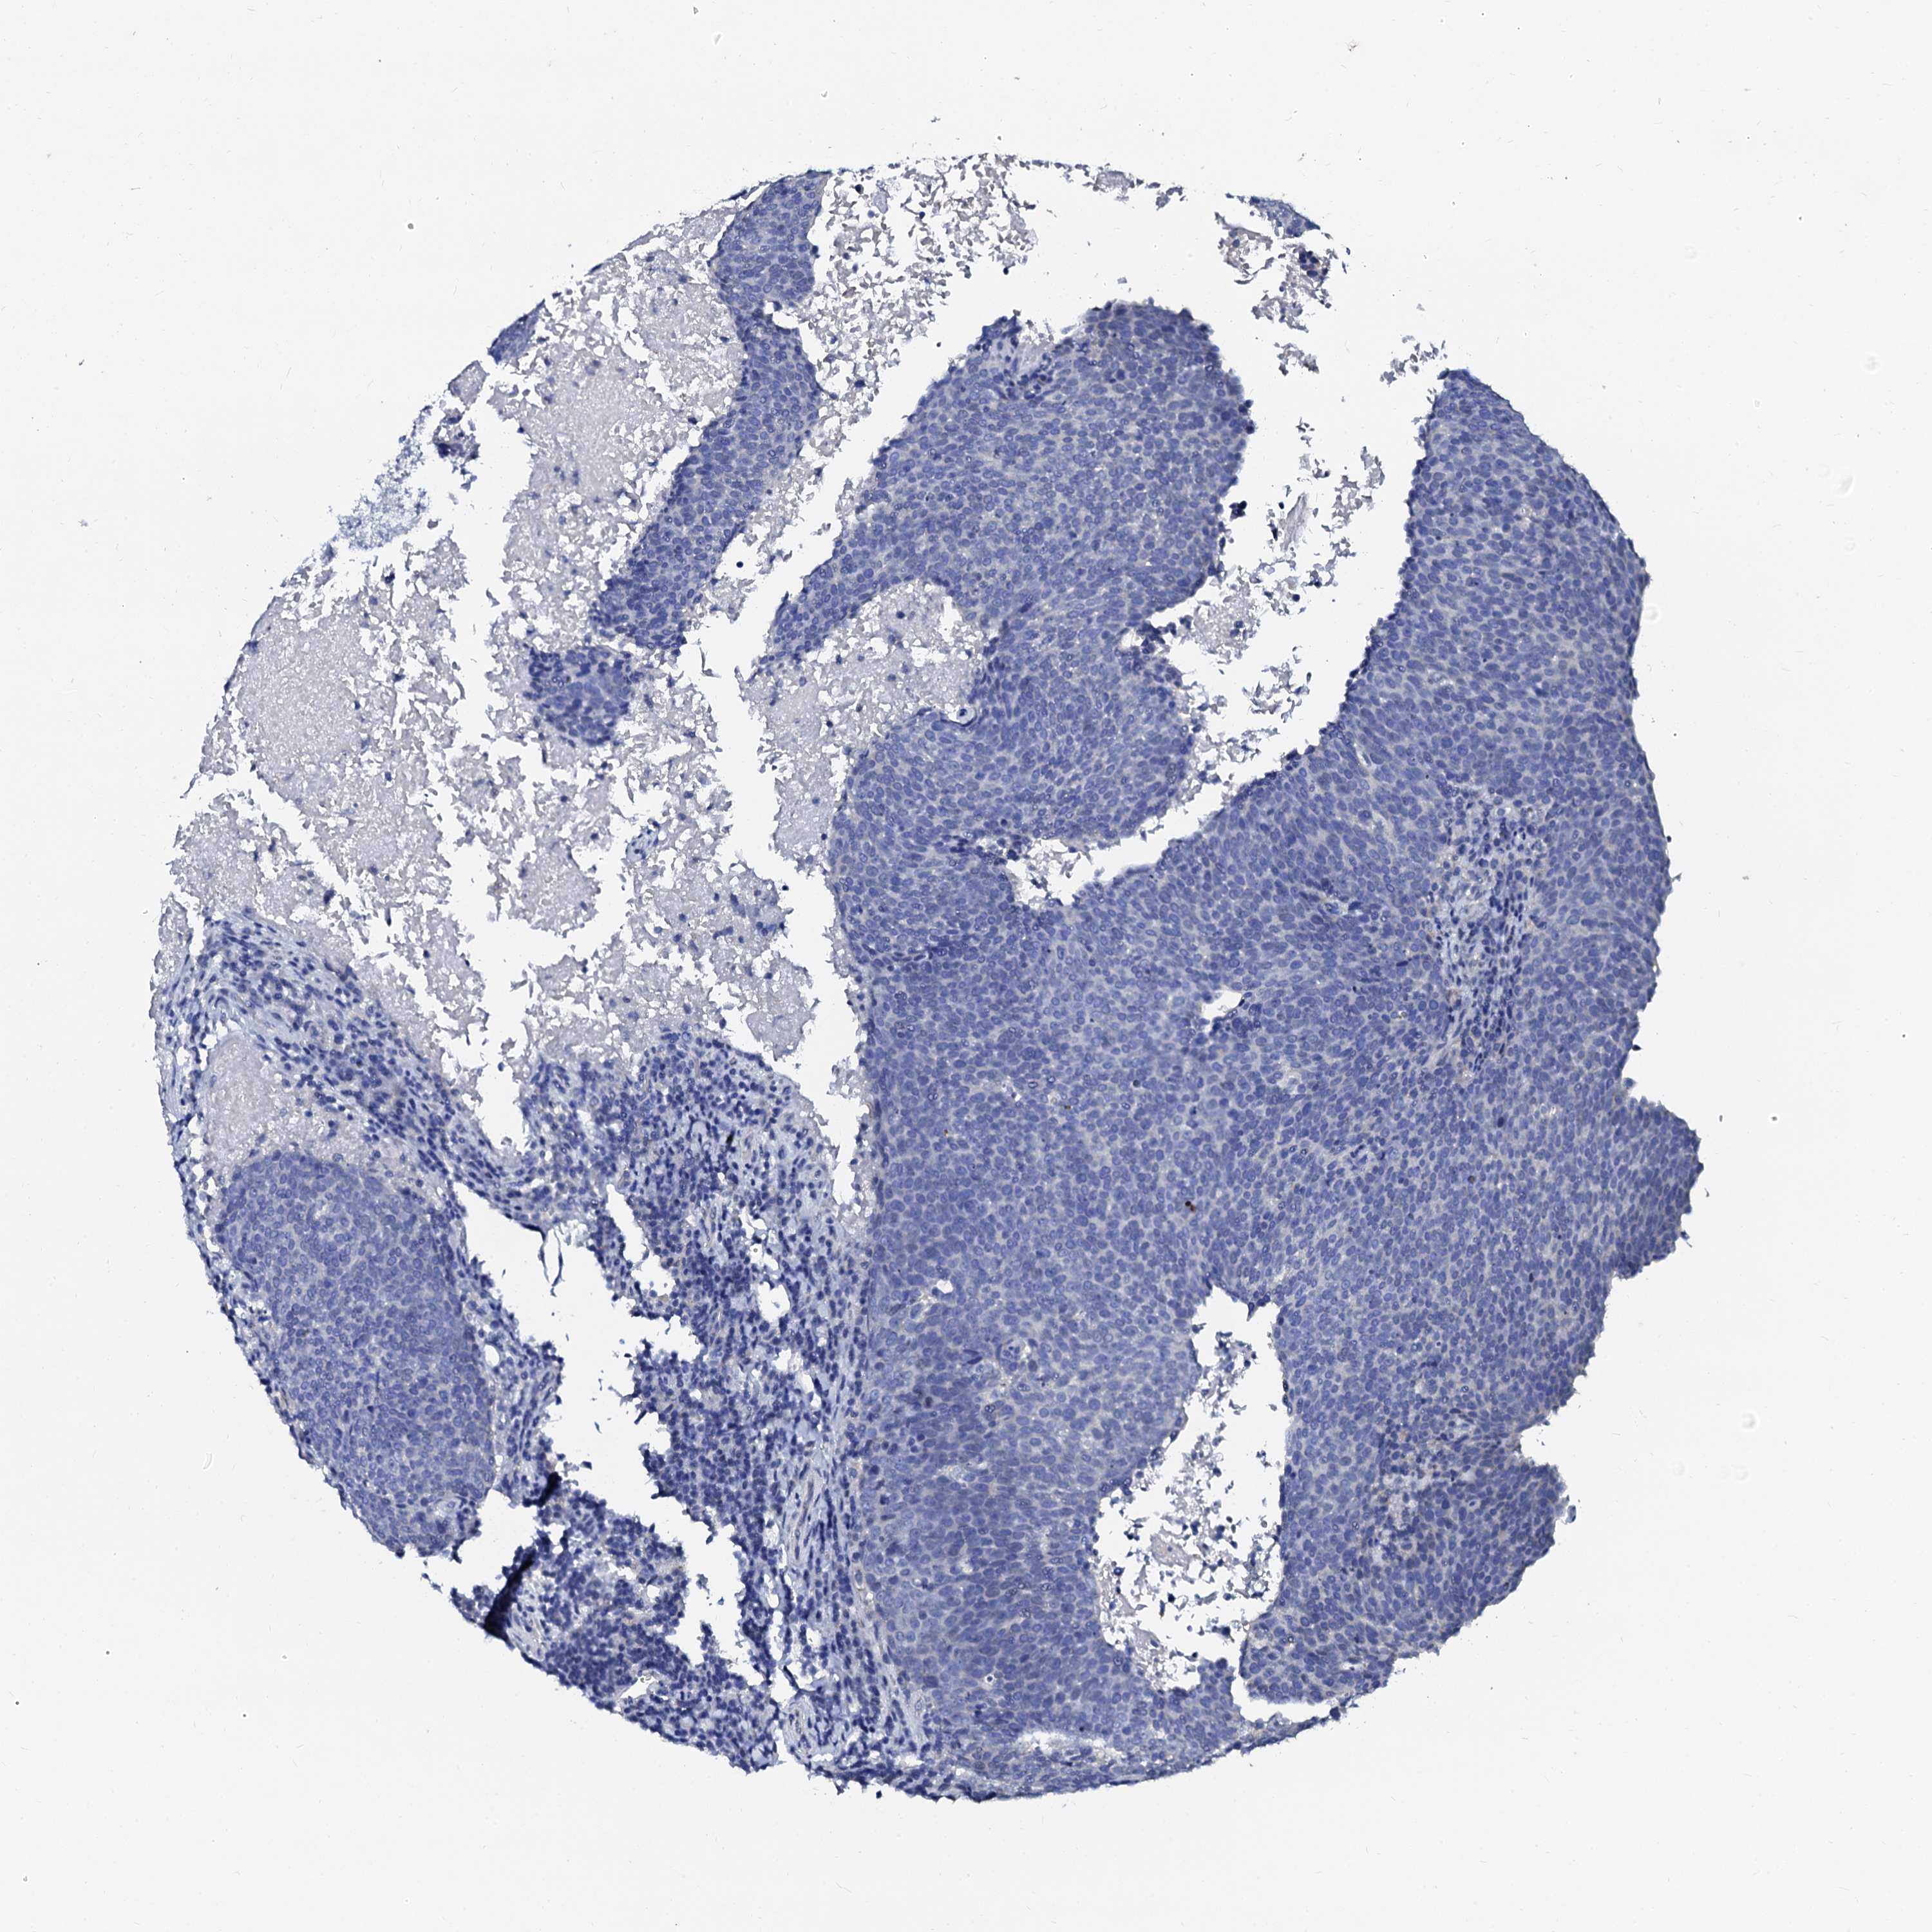

HEAD AND NECK CANCER - Protein expressioni

A mouse-over function shows sample information and annotation data. Click on an image to view it in a full screen mode. Samples can be filtered based on level of antibody staining by selecting one or several of the following categories: high, medium, low and not detected. The assay and annotation is described here.

Antibody stainingi

Antibody staining in the annotated cell types in the current human tissue is reported as not detected, low, medium, or high, based on conventional immunohistochemistry profiling in selected tissues. This score is based on the combination of the staining intensity and fraction of stained cells.

Each image is clickable and will lead to virtual microscopy that enables deeper exploration of all samples and also displays staining intensity scores, fraction scores and subcellular localization as well as patient and tissue information for each sample.

Antibody HPA038939

Staining

High

Medium

Low

Not detected

Intensity

Strong

Moderate

Weak

Negative

Quantity

>75%

75%-25%

<25%

None

Location

Nuclear

Cytoplasmic/membranous

Cytoplasmic/membranous,nuclear

Squamous cell carcinoma, NOS

Squamous cell carcinoma, metastatic, NOS